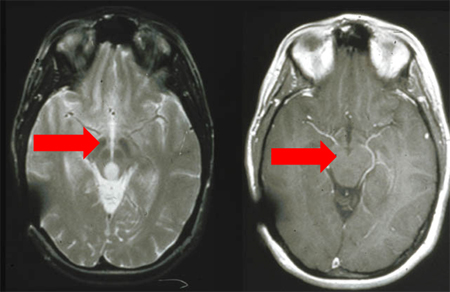

RNM: T2 e T1 pós-contraste, demonstrando glioma do teto mesencéfalo (grau II).

Do acervo pessoal de Karine Michaud, University of California, San Francisco; usada com permissão